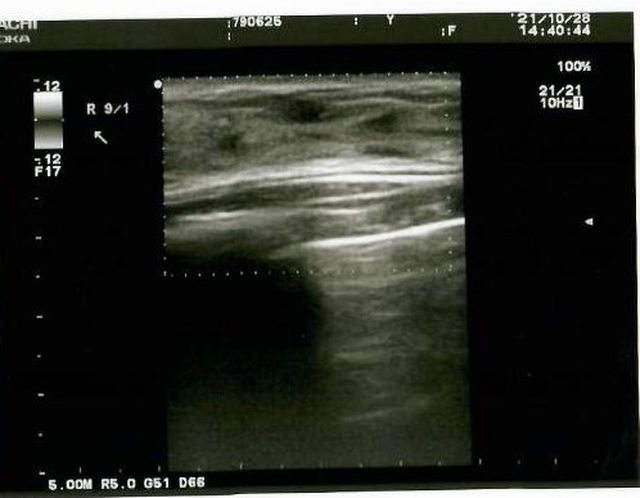

就立即幫我安排做乳房的超音波檢查

超音波室中乾淨隱密 病患可以放心

因為超音波範圍不大 所以使用的探頭較小

透過儀器的檢查發現在右側乳房有一個纖維囊腫

雖然不是看得很明白 但是跟左邊胸部的超音波畫面比起來確實多了東西